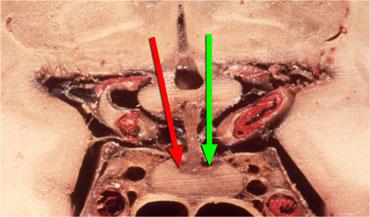

Các hình ảnh này mô tả phẫu thuật cắt bỏ u tuyến yên đại tuyến qua đường xuyên bướm (transsphenoidal resection).

Sau khi phần sàn xương của hố yên được lấy bỏ, màng cứng (dura) được rạch bằng đường rạch hình chữ thập.

Do áp lực phía trên màng cứng lớn hơn áp lực phía dưới, khối u đại tuyến sẽ tự thoát ra vào xoang bướm (sphenoid sinus).